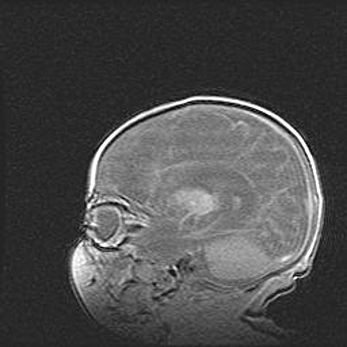

Сообщающаяся гидроцефалия. Кистозная энцефаломаляция головного мозга.

Возраст: 3 месяца 4 дня

Вес: 3100 г

Пол: женский

Окружность головы: 34 см

Срок гестации: 31 неделя

Кистозная энцефаломаляция головного мозга - одна из форм поражения головного мозга в детском возрасте. Характеризуется возникновением множественных и распространённых кист в коре, белом веществе и подкорковых образованиях головного мозга у плодов, новорождённых и детей раннего возраста. Развитие кистозной энцефаломаляции связано с внутриутробной асфиксией и гипотонией, родовой травмой, тромбозом синусов, пороками развития сосудов, инфекциями, сепсисом и другими причинами. Наиболее значимые инфекционные агенты: вирусы простого герпеса, цитомегалии, краснухи, токсоплазмы, энтеробактерии, золотистый стафилококк и другие.